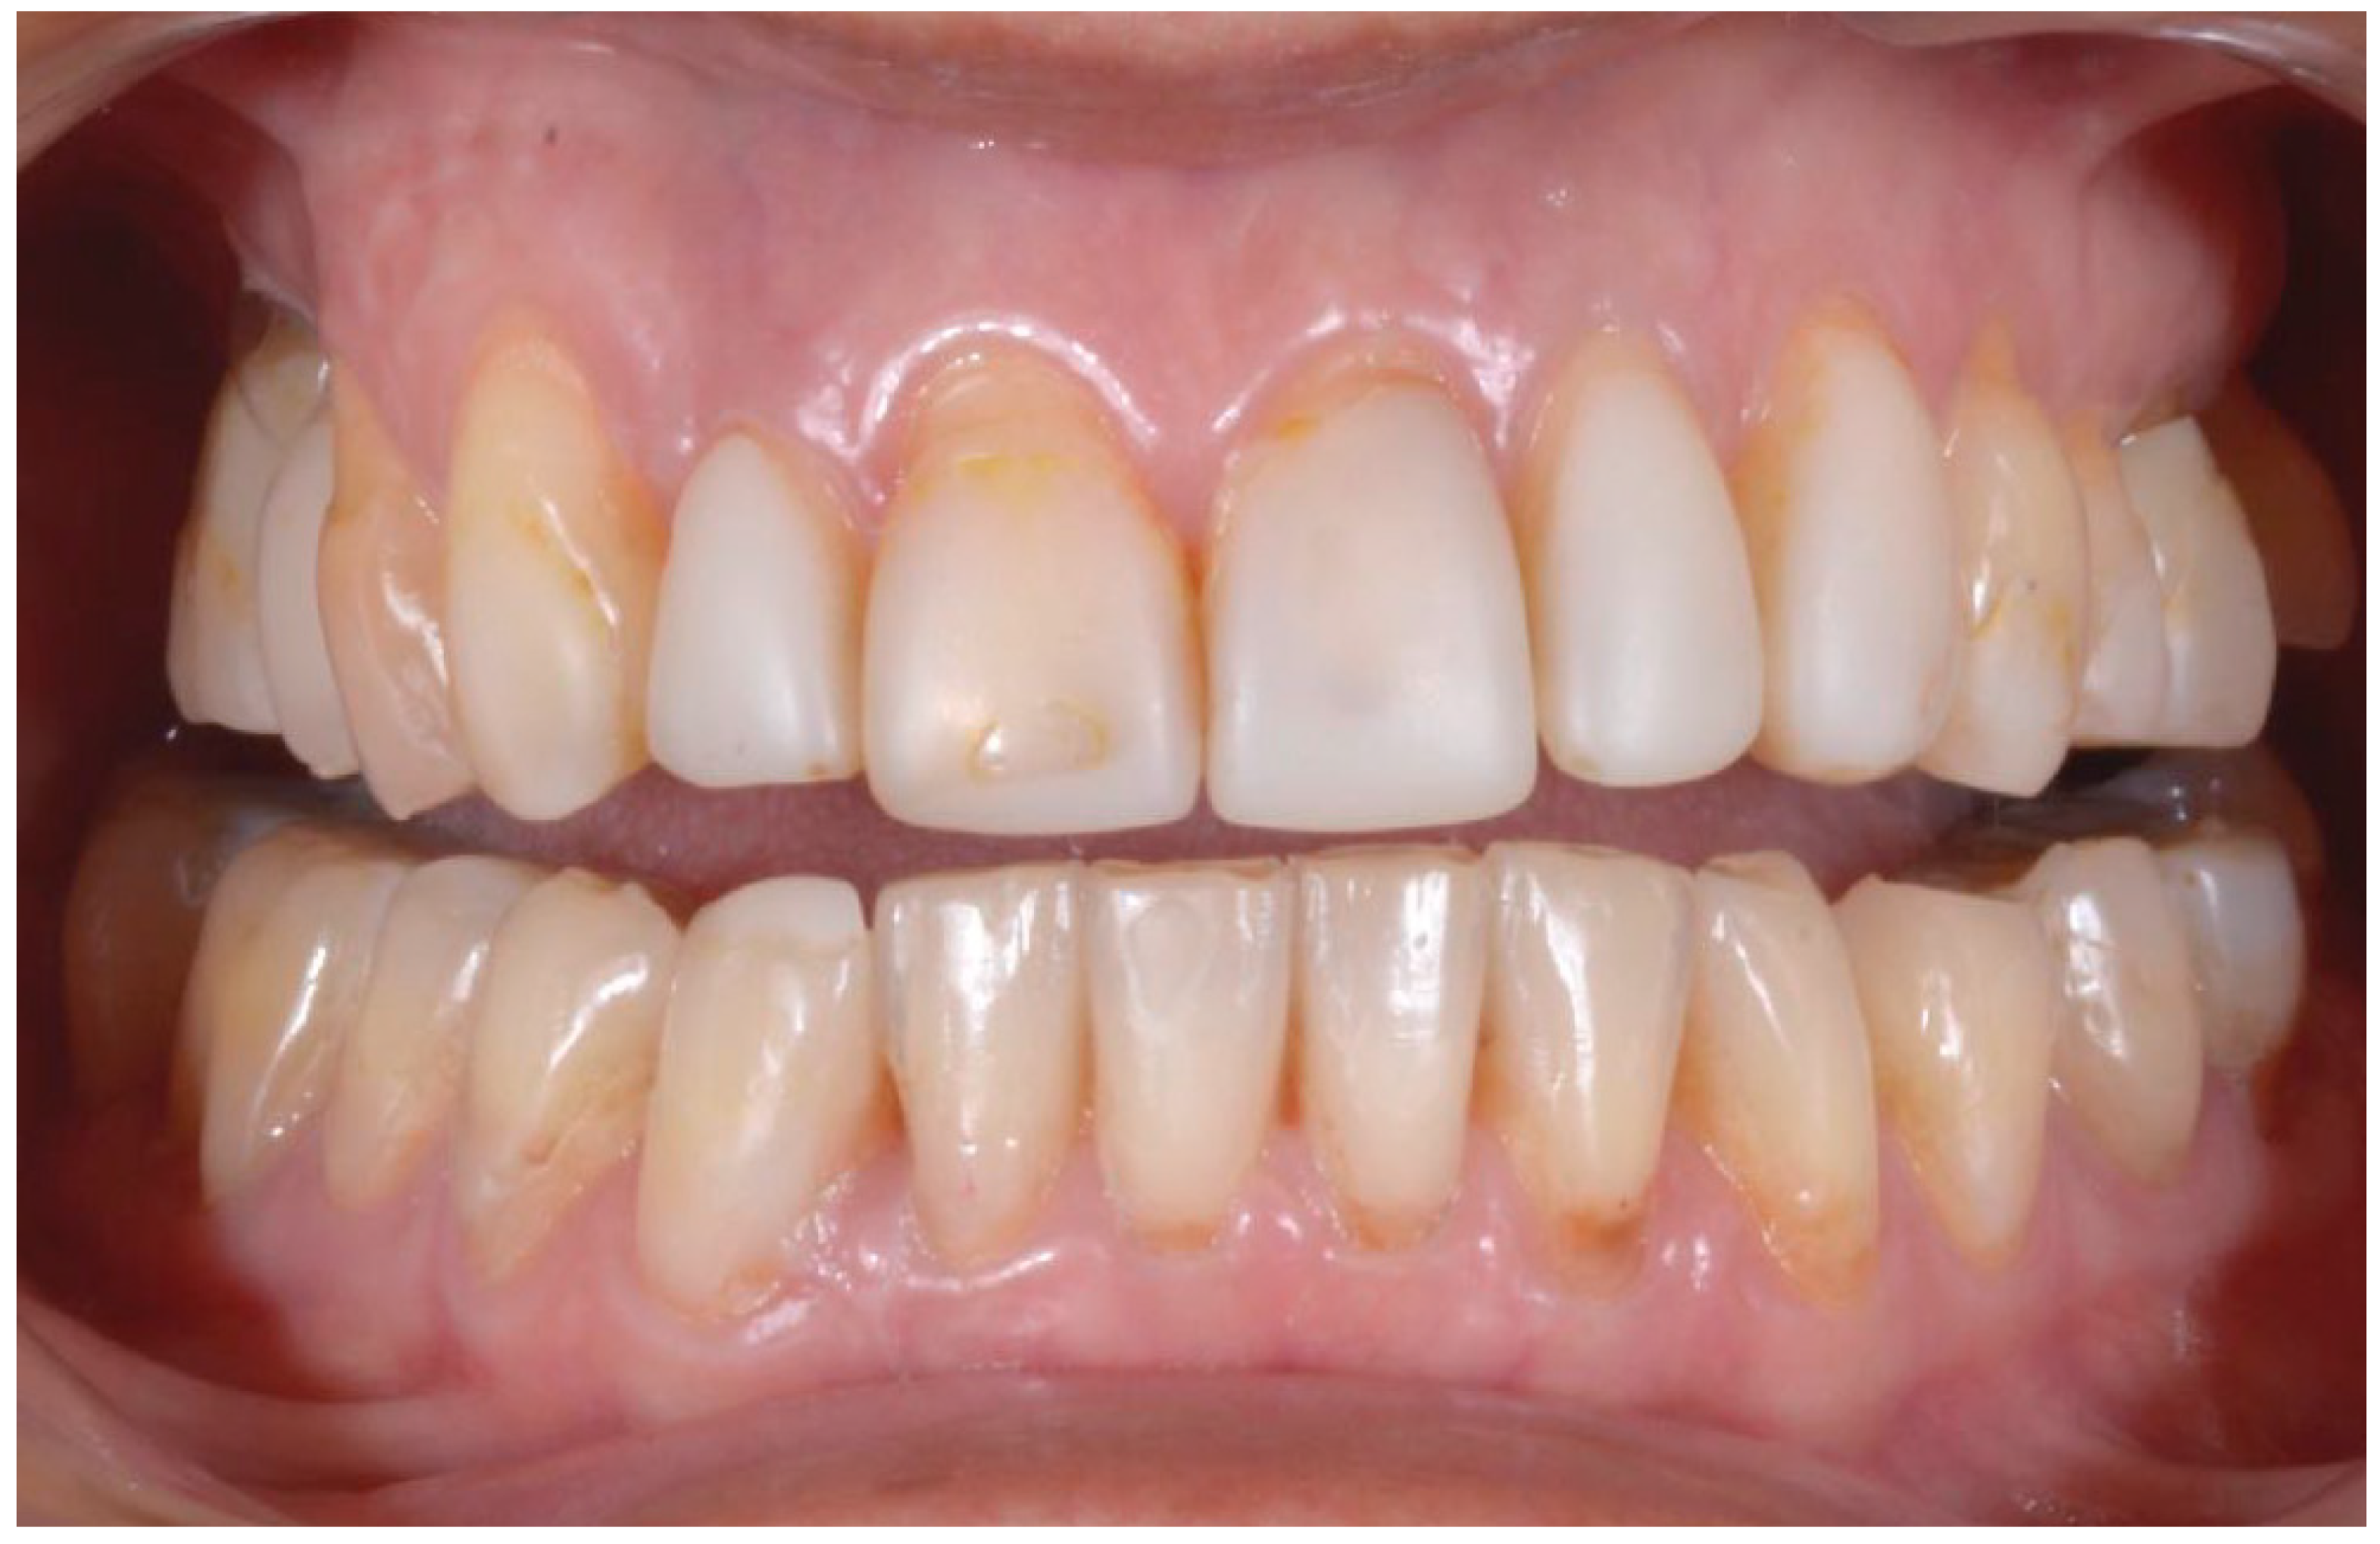

2.2. Clinical Example

| Disharmonious smile | Yes | No |

| Dyschromia, dysmorphia, abrasions, and erosions of teeth | Yes | No |

| Anterior crowding in the upper arch | Yes | No |

| Anterior crowding in the lower arch | Yes | No |

| Upper transverse discrepancy | Yes | No |

| Presence of buccal corridors or black tunnels | Yes | No |

| Curve of Spee alteration | Yes | No |

| Curve of Wilson alteration | Yes | No |

| Functional movements with altered guides | Yes | No |

| Pain and/or noise ATM | Yes | No |